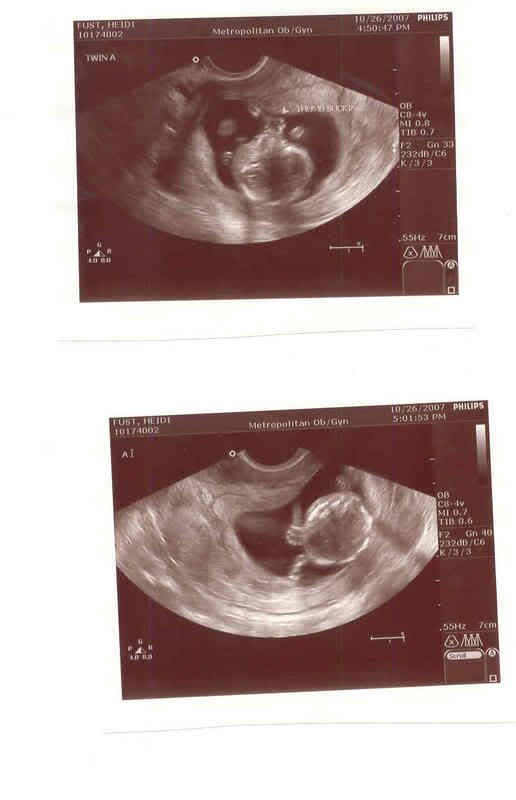

| More baby pictures |

Baby A Sucking His/Her Thumb, and waving hello!!!